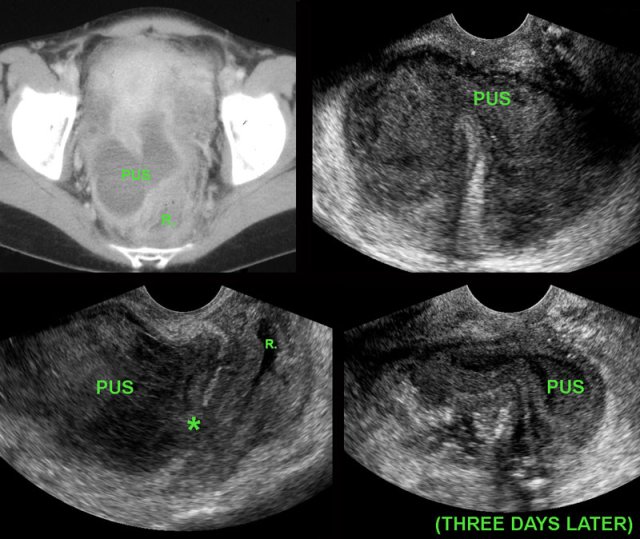

Spontaneous evacuation of postoperative Douglas abscess to rectum. Spontaneous evacuation of postoperative Douglas abscess to rectum.

Deep pelvic abscess

Young woman with abdominal pain and fever 10 days after surgery for perforated appendicitis.

CT shows a bilobar puscollection, close to the thick-walled, empty rectum (R.).

TVUS confirms the abscess, and demonstrates an echolucent tract (*) from the abscess towards the rectal lumen (R.)  with focal blurring of the layer structure of the oedematous rectal wall.

These TVUS findings, in combination with the improving symptoms of the patient, are signs of impending spontaneous evacuation.

Three days later the thick-walled abscess is almost empty.

The patient recovered without surgical or radiological drainage.